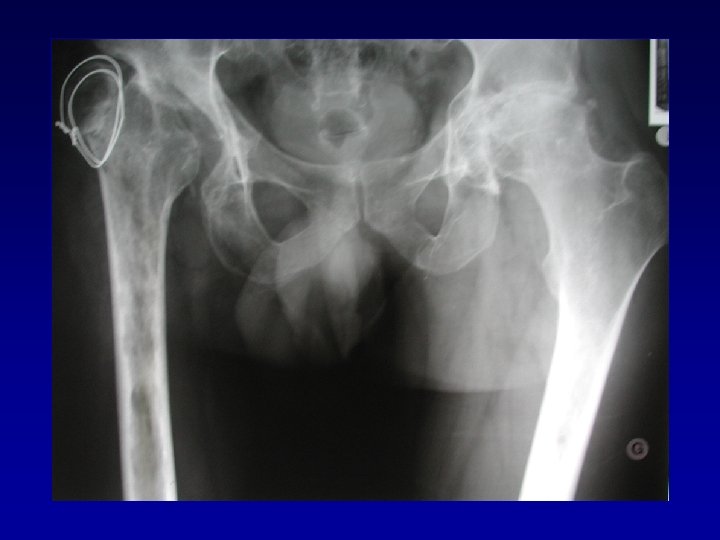

Bilan • • Type de fracture du cotyle Déformation de la cavité cotyloïdienne Chirurgie préalable Raideur Ostéome Nécrose de la tête fémorale Luxation invétérée

Déformation du cotyle • Ascensionné • Perte de substance osseuse scanner • Pseudarthrose •

Déformation du cotyle • Ascensionné • Perte de substance osseuse scanner • Pseudarthrose • Perte du positionnement exact (idem LCH) • Doit être reconstruit et recentré